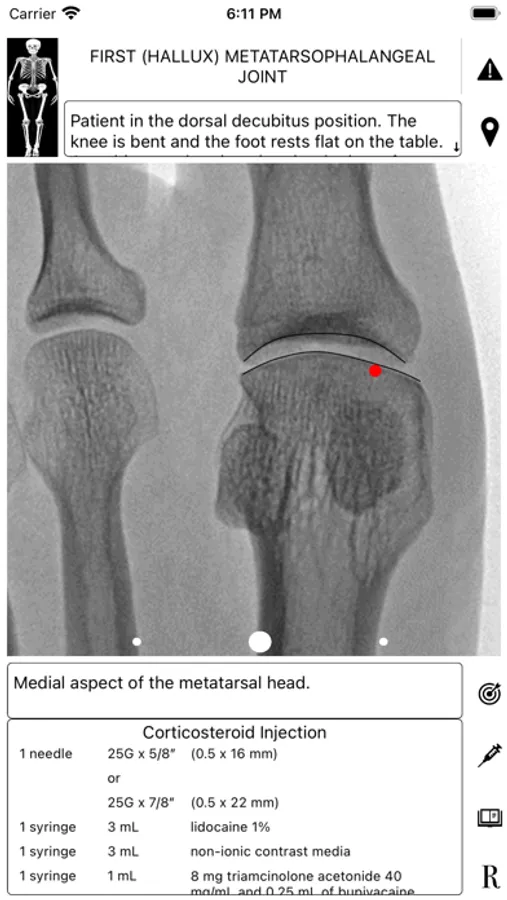

ArthroGuide targets residents, fellows, and physicians who perform fluoroscopically guided arthrograms and pain management injections, including spinal injections. It results from more than 25 years of experience in performing and teaching these procedures.

A visual interface facilitates a quick and efficient review of the information. Find information on patient positioning, puncture site, equipment used, products injected, and the steps to perform therapeutic injections and arthrograms preliminary to an MRI or CT scan. Access relevant references online using hyperlinks directly from within the application. Take advantage of procedural tips, recommendations, and cautionary statements.

ArthroGuide Screenshots